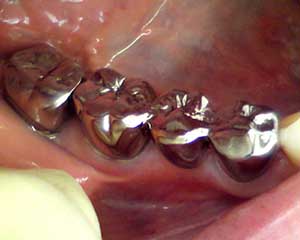

■えー、僕が基本的にあんまり銀歯を入れたくない人なもんで、当院では

可能な限り保険内でも

白い歯を入れるよう努力しています

(もちろん自費治療もやってます)。

★でも別に銀歯が悪いものとかいうわけでは全くなく、セラミックと比べても

銀歯の方が強度は高いし、欠けないし、長持ちすることも多いです。

ただ、審美的な欠点や掌蹠膿疱症などの金属アレルギー問題もあり、強度的に問題が

ない部分であればプラスチックやセラミックで代替できれば、みんな幸せかなぁと。

■まあそんなわけで「口の中に入っている銀歯を白い被せ物にやりかえたい

といったご要望にも、保険・自費共に可能な限り対応させていただいておりますので、

お悩みの方はぜひ一度気軽にご相談下さい。(

★ご要望に添えない場合もあります)